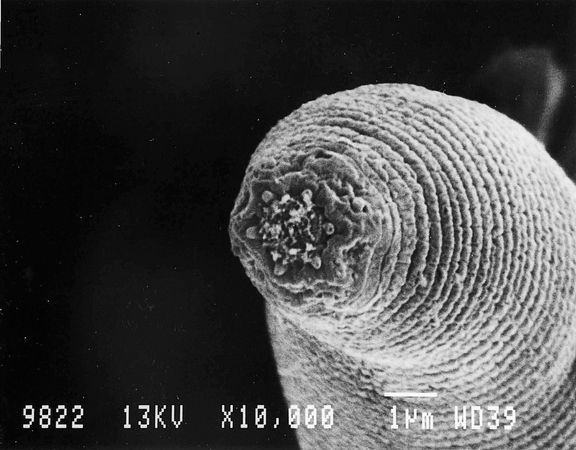

▼4.福氏耐格里變形蟲(Naegleria fowleri),又被稱為食腦菌、食腦變形蟲。

▼這種寄生蟲生存範圍廣泛,幾乎全球的淡水水域都能找到牠們的身影。人們游泳時,牠們會沿著鼻子進入大腦,然後以大腦為食。一旦被這種寄生蟲入侵到腦部,沒有任何治療的方法,致命率高達99%。

在顯微鏡下,牠看起來就像一個「笑臉」,所以也被稱為「死亡微笑」。不要以為這種寄生蟲距離我們很遙遠,2011年時,一名75歲阿公因為泡溫泉被感染,發病25天後離開了世界。